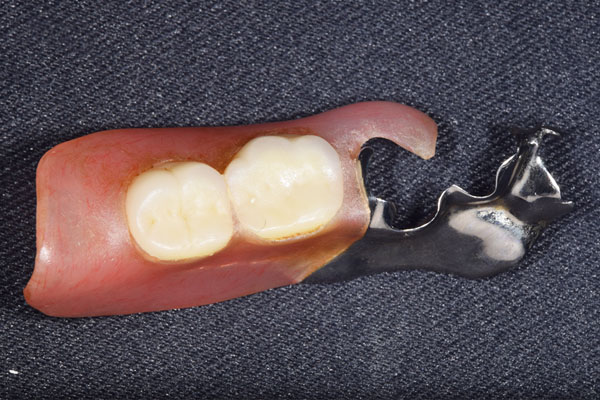

こちらが完成したかぶせ物と入れ歯です。かぶせ物にはアタッチメントをつけて金属のバネが見えない構造になっています。 入れ歯自体も金属を使用して、極力違和感がでないように、薄く作成しました。

お口の中に入れた状態です。 非常に見た目もよい出来となりました。 バネがみえないと見栄えが全然ちがいます。

見た目が入れ歯とわからない様に針金のない、アタッチメントを使用した入れ歯を作成することにしました。